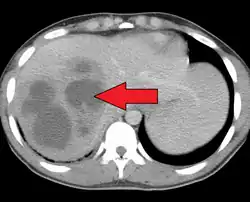

| Liver abscess on axial CT image: a hypodense lesion in the liver with peripherally enhancement. | |